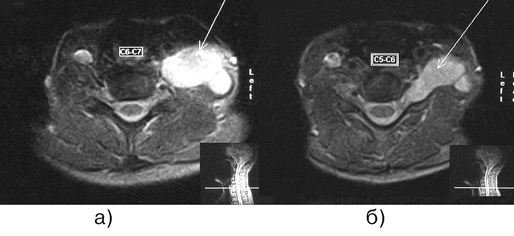

МРТ при шванномах и других новообразованиях в проекции нервного ствола выявляет гиперинтенсивное объемное образование; потерю фасцикулярного рисунка нервов в прилегающей области; участки ствола, граничащие с образованием, имеют гиперинтенсивный сигнал в T2 режиме. Шванномы представляют собой дольковые инкапсулированные округлые или овальные образования, гиперинтенсивные в T2-режиме, изо— или гиперинтенсивные в T1-режиме (рис. 1). Более чем в половине случаев в строме шванном выявляются участки некроза и кистозной дегенерации, они проявляются негомогенными гиперинтенсивными областями в T2-режиме. Нейрофибромы представляют собой неинкапсулированные грибовидные, менее четко отграниченные образования по сравнению со шванномами. Они также гиперинтенсивны в T2-режиме и изо-/гиперинтенсивны в T1-режиме (рис. 2). В отличие от шванном, нейрофибромы обычно не могут быть отделены от материнского нерва, т.к. нервные волокна проходят через опухоль.

Рисунок 1. Шваннома плечевого сплетения (МРТ, а — Т1, б — Т2-взвешенные изображения)